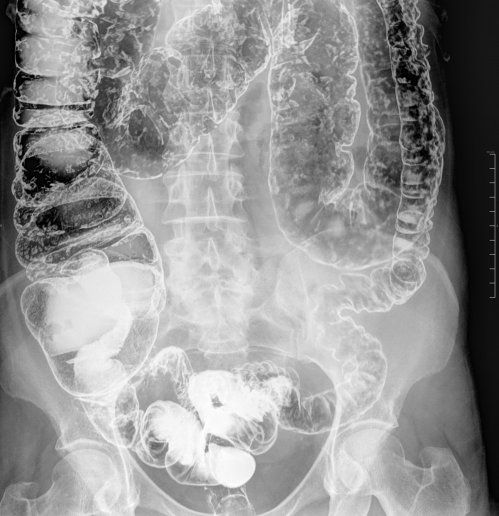

Enema de bario - Enema opaco

El enema de bario / enema opaco es un estudio con Rayos X del intestino grueso (colon) cuya finalidad es valorar la forma y la función del colon. La prueba consiste en introducir contraste de bario y a veces bario y aire, por vía rectal y simultáneamente obtener radiografías.

Se introduce el contraste lentamente y se realizan radiografías, en diferentes posiciones, que son vistas por el radiólogo en un monitor; a continuación se coloca la bolsa por debajo del nivel de la mesa de exploración para favorecer la salida del barrio y se introducirá una pequeña cantidad de aire. Finalmente pasará usted al aseo y terminará de eliminar el resto de bario que pudiera quedar en el colon y se realiza una última radiografía tras la evacuación.